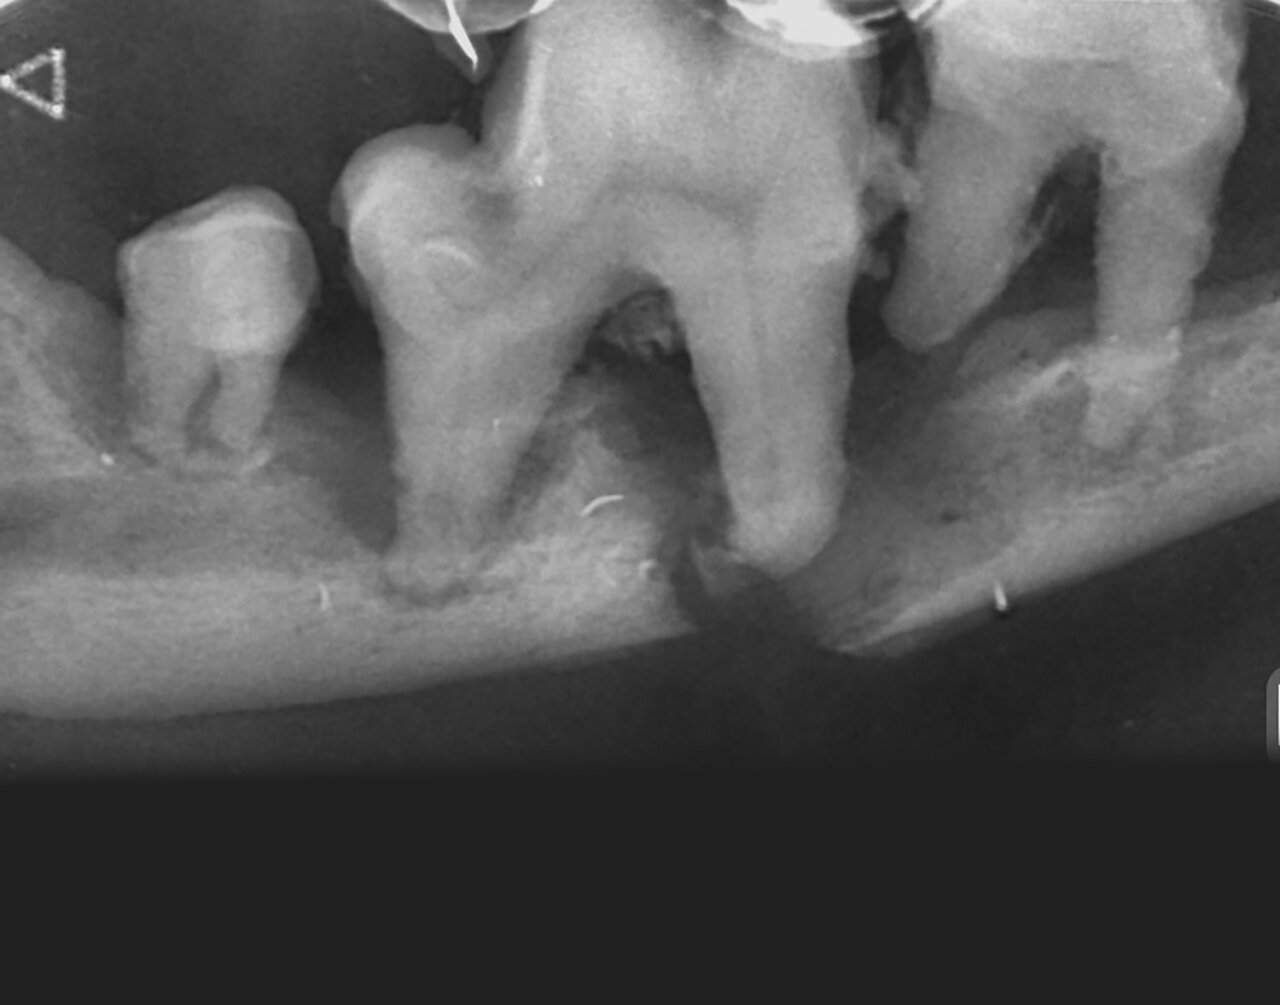

Además de permitirnos evaluar el grado de enfermedad periodontal, también hace posible seleccionar el mejor tratamiento en función de su patología y las posibles complicaciones, como las fracturas mandibulares iatrogénicas en perros de talla pequeña con enfermedad periodontal PD4 (imágenes 10 y 11).

Fracturas dentales

Las radiografías son esenciales en la detección y evaluación de las fracturas del hueso (alveolar, maxilar y mandibular) y del diente (tanto a nivel de la corona, para ver su relación con la pulpa, como de la raíz dental). Los dientes rotos o fracturados son un problema muy común en la práctica veterinaria.

El tratamiento, a menudo, depende de qué partes del diente estén afectadas, raíz y/o corona, y en el caso de esta última, de qué capa(s): esmalte, dentina y si hay exposición o no de la pulpa:

- Las fracturas que no afectan directamente el sistema del conducto radicular se denominan fracturas de corona no complicadas, aunque hay que tener en cuenta que la exposición de los túbulos dentinarios de la dentina puede actuar como vía de entrada de gérmenes y también originar las alteraciones endodónticas (imagen 20).

- Las fracturas que exponen el canal radicular se denominan fracturas complicadas y estos dientes con exposición directa de la pulpa deben tratarse mediante endodoncia o extracción (imágenes 21 y 22).

Cuando la fractura afecte a la raíz del diente este debe ser extraído (imagen 23).